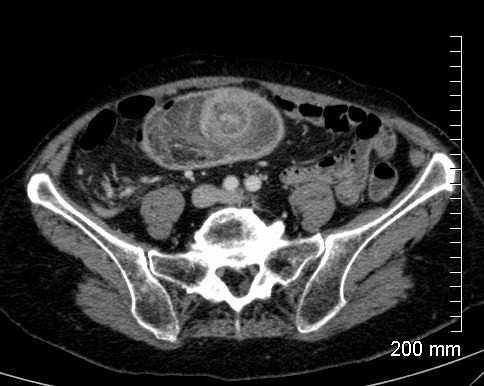

Le patient a une diverticulite. Devant persitance fièvre et augmentation du sd inflammatoire à 48h on réalise le TDM suivant. Vu la taille de l’abcès (>5 cm on va dire), quelle CAT?

drainage de l’abcès: ponction percutanée écho ou scanno-guidée; OU drainage chirurgical si percut impossible (avec RDC à distance)